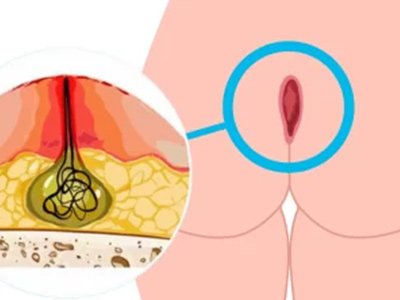

Cisto pilonidal

Exérese de cisto pilonidal

Cisto Pilonidal com Laser